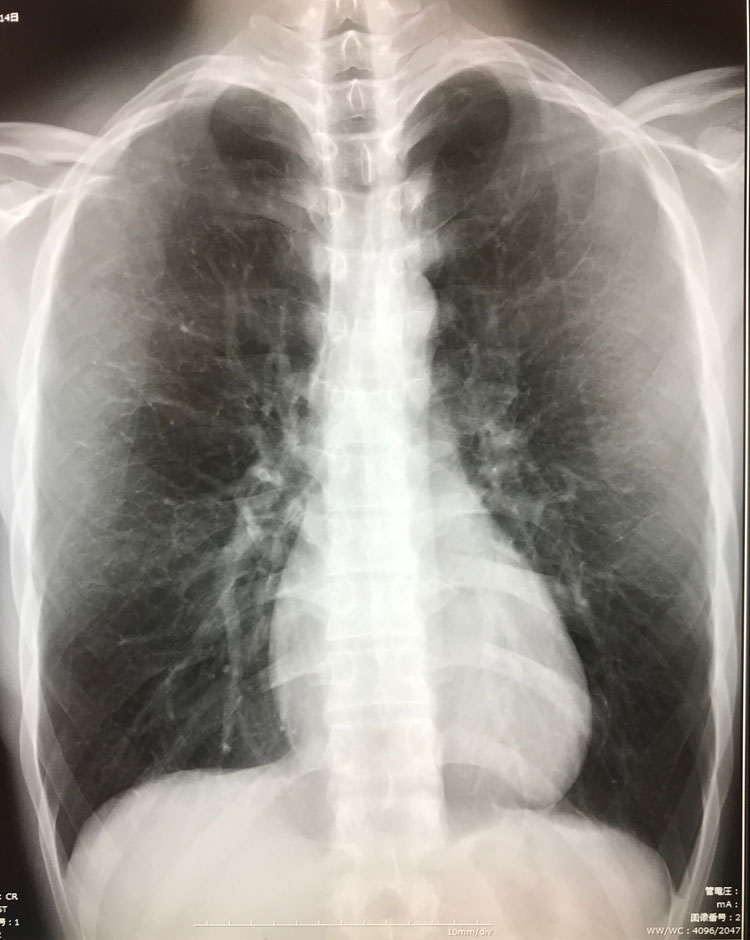

レントゲン

当院のデジタルX線撮影装置は、X線撮影画像を瞬時に処理し即座に画像表示することができます。

瞬時に診断画像を表示できますので、患者様の検査時間を約4分の1に短縮できます。また、従来のX線撮影に比べて約半分の被ばく線量できめ細かな診断画像を作成できるため、患者様の負担を大幅に低減することができます。

胸部レントゲン写真には肺にある骨に重なった病変が見やすくなる画像処理技術(Bone Suprpession)を導入し、診断の精度向上に役立てております。